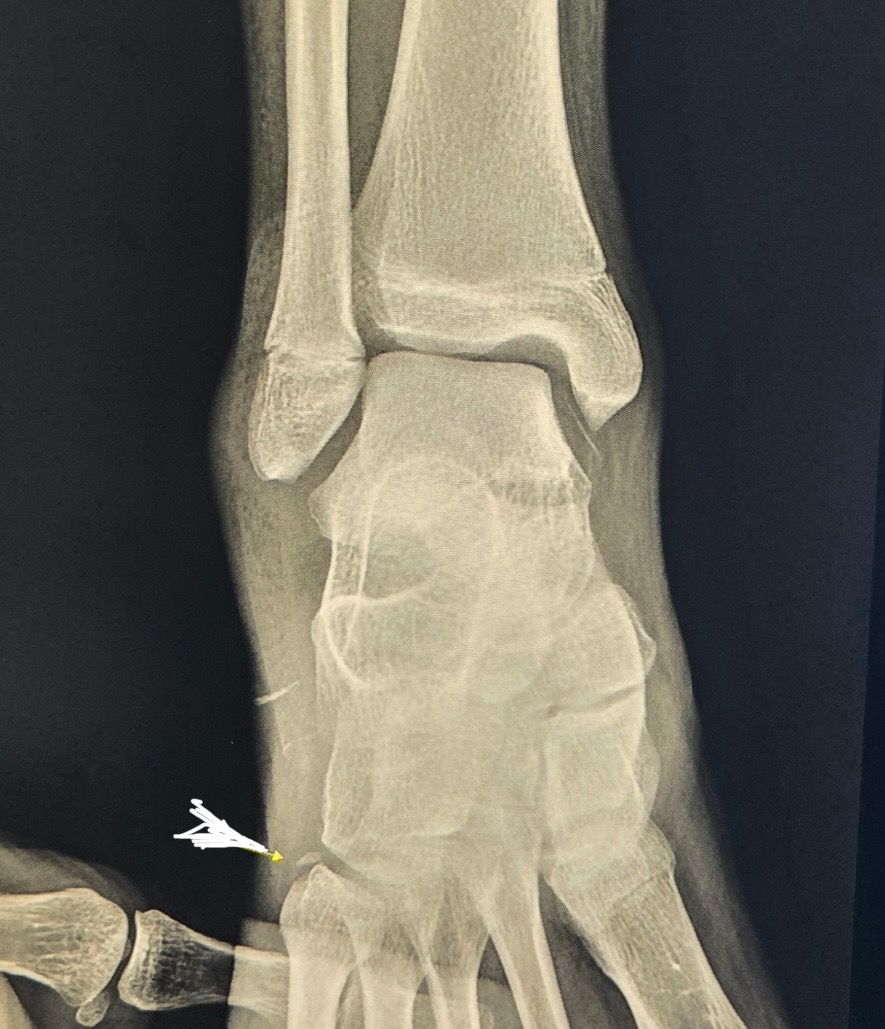

아이가 운동하다가 착지할때 발을 헛딛어서 발등뼈와 연결된 새끼발가락 끝쪽을 다쳤어요. 끝쪽뼈가 손톱 반만하게 떨어져나가 조금 떨어진 자리에 있는데 별다른 조치없이도 시간이 지나면 제자리 찾아 붙을까요? 병원에서는 지켜보자 했는데 이런경우 제자리를 찾아 정확히 붙는지 아니면 다른 치료법을 찾아봐야하는지 궁금합니다

• 1번 째 사진